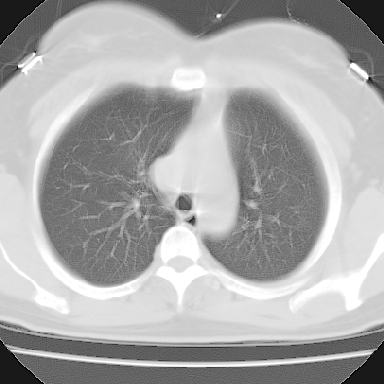

左下肺肿块影,内可以见小泡征,并见厚壁空洞形成,洞内缘凹凸不平,可见壁结节。靠近胸膜侧可见胸膜凹陷征。左侧胸腔内可见少量低密度积液影。双肺可见多发性小结节影。

考虑:左下肺癌性空洞伴两肺转移

左下肺肿块影,内可以见小泡征,并见厚壁空洞形成,洞内缘可见壁结节。靠近胸膜侧可见胸膜肥厚粘连。双肺可见多发性小结节影。

考虑:左下空洞性肺癌伴两肺转移

左下肺有空洞,壁厚薄不均,壁结节,两肺多发小结节影,腋窝下可疑淋巴结肿大,综上所述考虑周围性肺癌并两肺转移可能性大,建议穿刺活检。

右肺多发小结节影,边界清楚,符合转移瘤的特点;2、左下肺偏心性空洞影,右侧乳腺内高密度影,需要查体除外右侧乳腺肿瘤;3、腋窝淋巴结肿大,考虑转移。